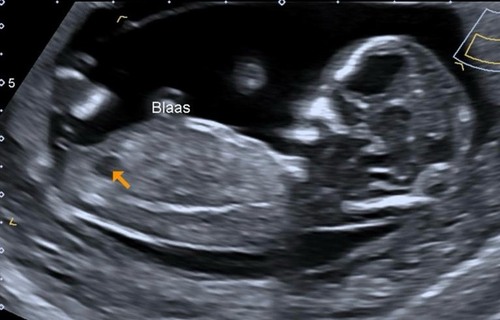

Nog een foto naar aanleiding van vorige bericht. Hier ziet het er weer anders uit dan de vorige foto

Oops ik had de verkeerde foto geüpload, dit is de juiste 😳